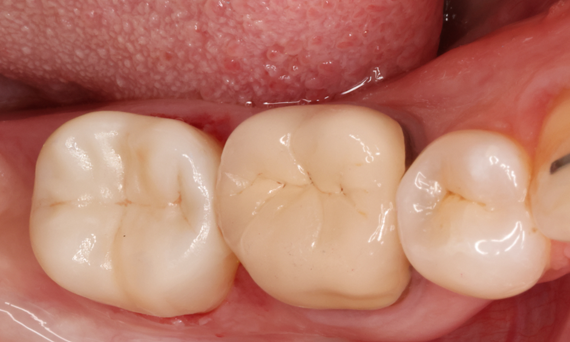

Before: Pre-operative clinical scenario after endodontic therapy.

After: 1 month after the CEREC Tessera onlay was bonded.

Second lower right molar in 90 minutes

A CEREC Tessera onlay

A 20-year-old female patient had endodontic treatment of her lower right 2nd molar. A chairside onlay was fabricated from the new high-strength ceramic CEREC Tessera ALD.

Dr. Aniruddha Nene

Pune, India